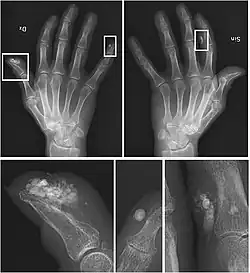

| CREST syndrome (calcinosis and sclerodactyly) | |

CREST causes thickening and tightening of the skin with deposition of calcific nodules ("calcinosis").

Though it is the most easily recognizable manifestation, it is not prominent in all patients. Thickening generally only involves the skin of the fingers distal to the metacarpophalangeal joints in CREST. Early in the course of the disease, the skin may appear edematous and inflamed. Eventually, dermal fibroblasts overproduce extracellular matrix leading to increased tissue collagen deposition in the skin. Collagen cross-linking then causes a progressive skin tightening. Digital ischemic ulcers commonly form on the distal fingers in 30–50% of patients.[3]